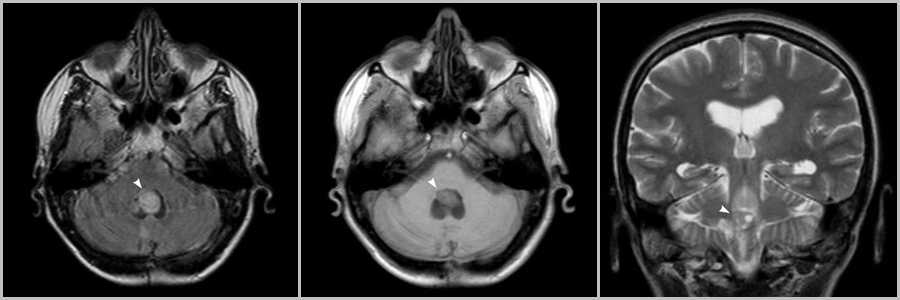

Хориоидпапиллома

Хориоидпапиллома заполняет IV желудочек, характеризуется фестончатым контуром, гиперпродукцией ликвора и расширением желудочковой системы, и не поражает мозжечок. При перфузионном исследовании показатели гемодинамики существенно превышают те же показатели у пилоцитарной астроцитомы, однако они ниже, чем гемангиобластомы.

Рис.11

Внутрижелудочковая масса в просвете IV желудочка (головки стрелок на рис.11), связанная с сосудистым сплетением.

Эпендимома

Эпендимома имеет ячеистую структуру и при росте распространяется в отверстия Люшка и Мажанди, для нее более характерны петрификаты. Кистозные компоненты в эпендимоме встречаются реже, чем в пилоцитарной астроцитоме. При МР-спектроскопии соотношением метаболитов Cr/Cho пилоцитарной астроцитомы ниже, чем у эпендимомы. Интенсивность сигнала по T2 от солидного компонента аналогична ликвору в 50% случаев. У пилоцитарной астроцитомы солидный компонент изоинтенсивен серому веществу по Т2.

Рис.12

Внутрижелудочковое объёмное кистозно-солидное образование (стрелки на рис.12), растущее из области IV желудочка вдоль заднего края спинного мозга в позвоночном канале (головки стрелок на рис.12).